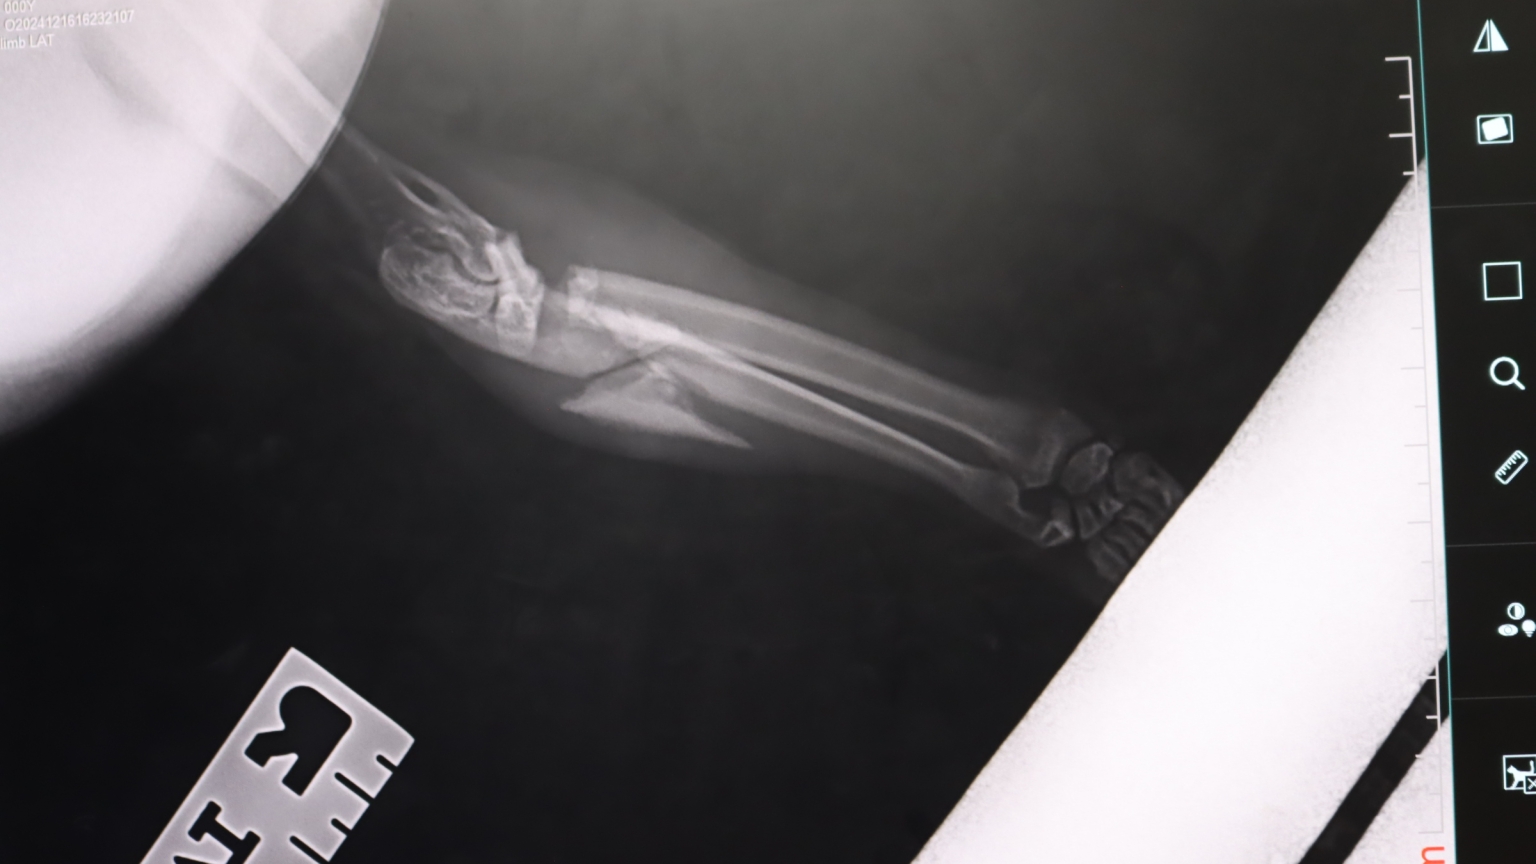

You were there for Kumo, a gentle stray with a severely broken leg.

Kumo